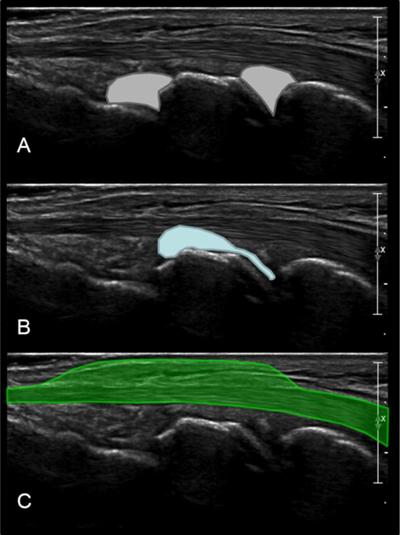

Figure 3

The role of the first sagittal view of carpal bones is to detect: (A) radiocarpal or mediocarpal joints effusions; (B) carpal ganglion cysts arising from the joint; (C) extensor tenosynovitis.